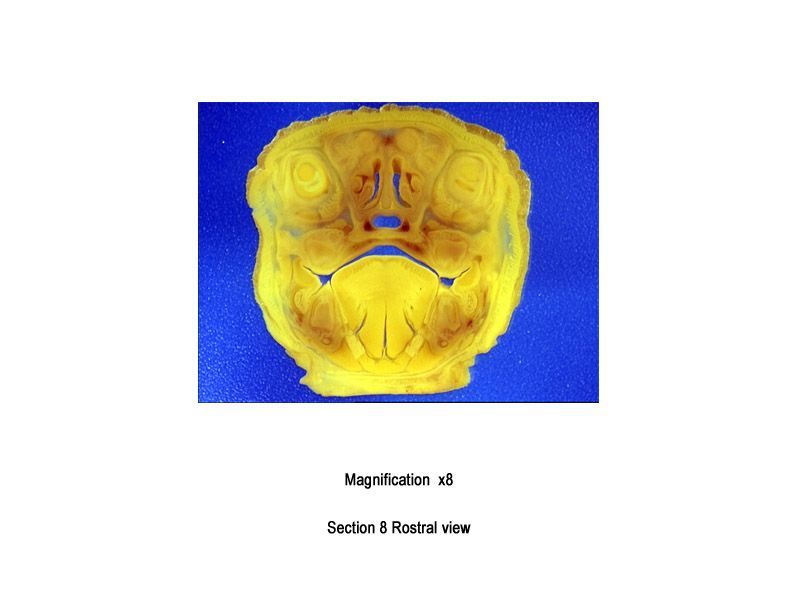

The images below show the normal appearance of Bouin's fluid fixed head sections in specimens at Day 29 of gestation (day mating observed = Day 0).

It is essential that both sides of each section is examined so that structures that exist is several sections can be visualised by the examiner in their mind as 3D.